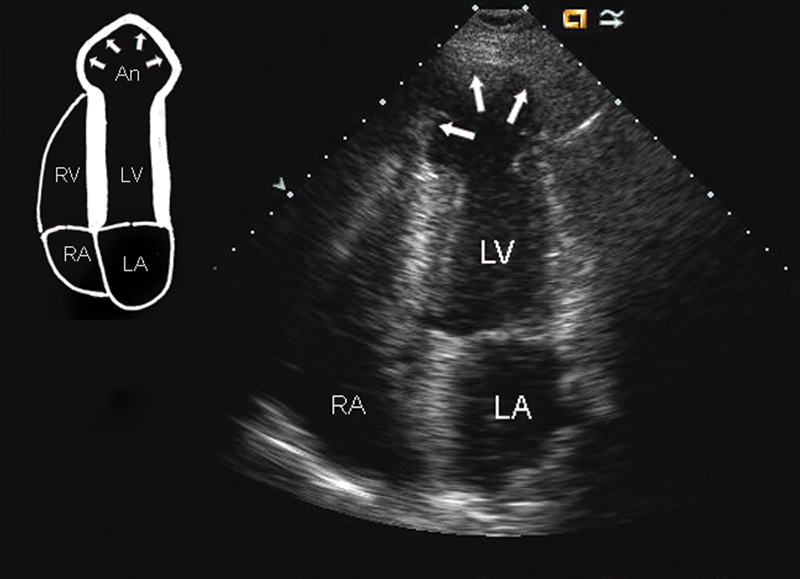

فحوصات تشخيصية لبعض امراض القلب والشرايين التاجية